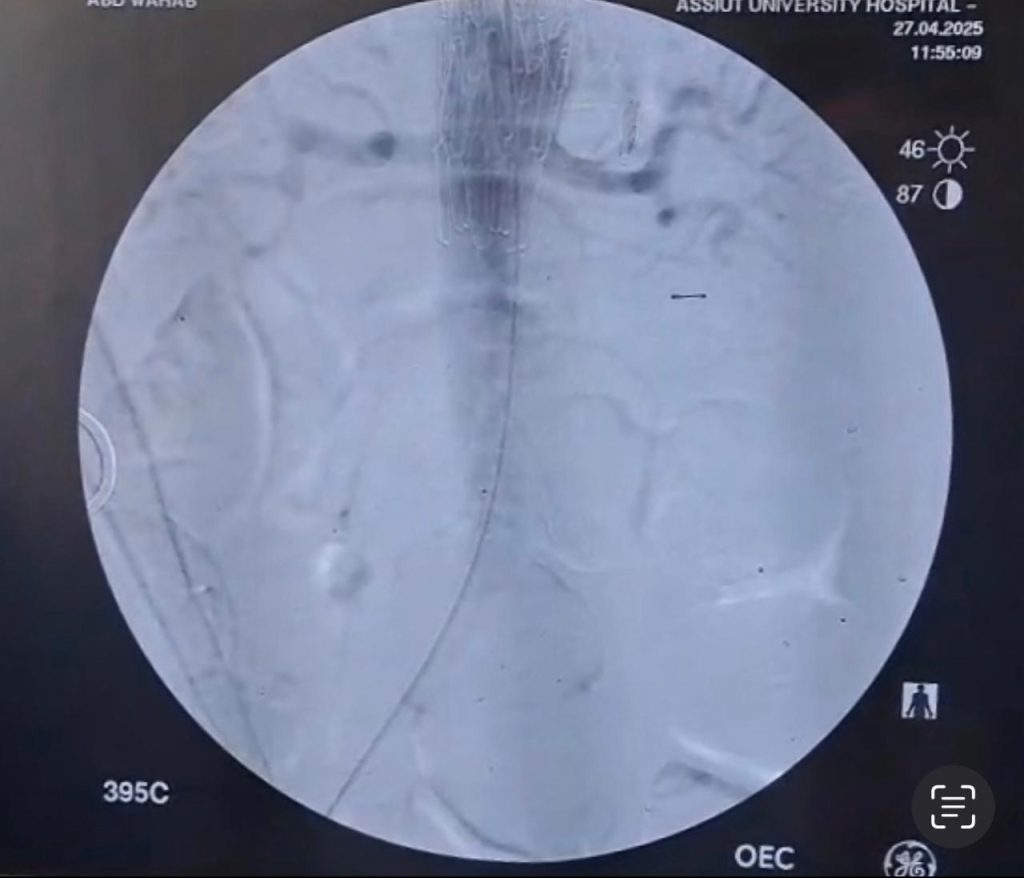

بينما تضمنت المرحلة الثانية استخدام القسطرة التداخلية بعد تخطيطا دقيقا وتنسيقا وثيقا بين التخصصات المختلفة، حيث قام الفريق الطبي بقسم جراحة الأوعية الدموية بالمستشفى الجامعى الرئيسى تحت إشراف الأستاذ الدكتور خالد عبد العزيز مدير المستشفى، وبرئاسة الأستاذ الدكتور هيثم علي حسن رئيس القسم، وضم كل من، الأستاذ الدكتور محمود إسماعيل، أستاذ جراحة الأوعية الدموية، والطبيب أحمد نجيب، مدرس مساعد بالقسم، بإجراء إصلاح للإنشطار بالشريان الأورطي الصدري والبطني باستخدام القسطرة التداخلية وتركيب دعامات مغطاة باستخدام تقنية (TEVAR).

وعقب ذلك قامت الأستاذة الدكتورة سلمى طه، أستاذ مساعد بقسم القلب، باستخدام تقنية التحفيز البطيني السريع من خلال تركيب منظم ضربات قلب مؤقت بالبطين الأيمن، والذى ساهم في تقليل حركة جدار الشريان الأورطي لزرع الدعامة المغطاة بالشريان الأورطي بدقة.